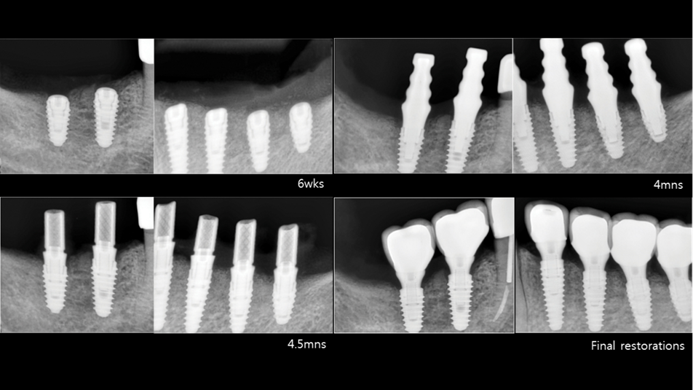

Klinikinis atvejis: Vėlyvoji implantacija: viršutinio žandikaulio ančio dugno elevacija, implanto sriegimas ir kraštinė kaulo regeneracija;

- Dr. Irfan Abas klinikinis atvejis -

Vėlyvoji implantacija, ančio dugno elevacija, ančio dugno elevacija atviru būdu, kraštinė kaulo regeneracija, Dr. Irfan Abas, AnyRidge, MiLA chirurginis rinkinys, kaulo regeneracija;

Clinical case: Installation of dental implants in complicated anatomic conditions using crest lifting methods

- Courtesy of Dr.Alexander Lysov, Russia -

AnyRidge, complicated anatomic conditions, crest lift, MICA Kit, Dr. Alexander Lysov, bone regeneration, GBR, #26, maxillary posterior